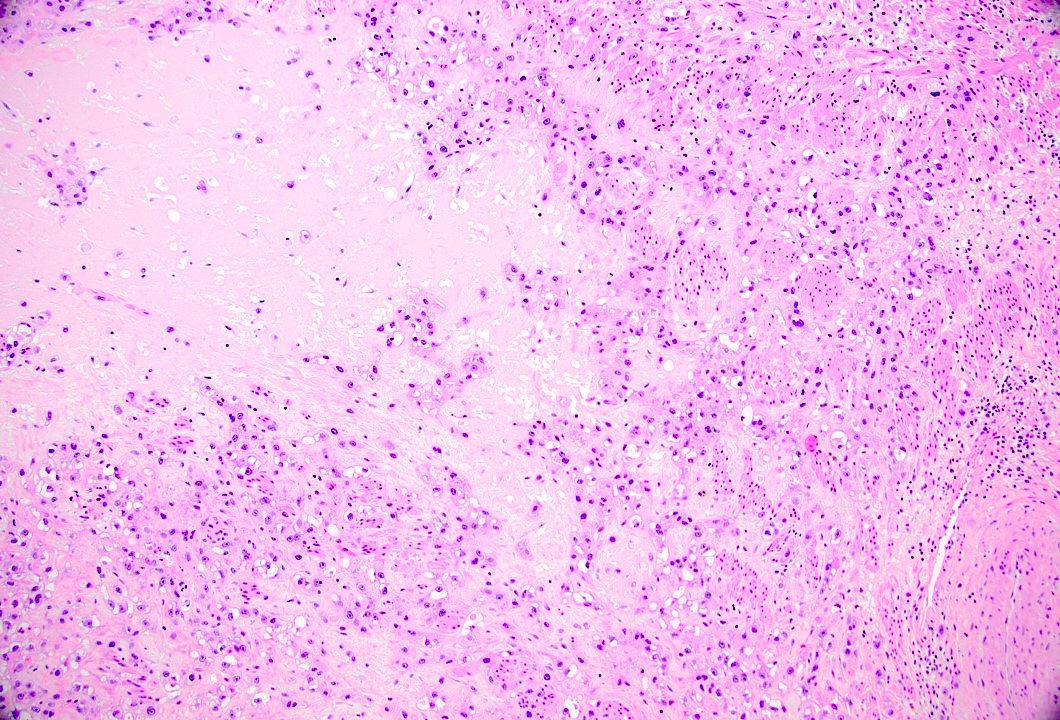

Microscopic (histologic) images

Contributed by Elizabeth Kertowidjojo, M.D., Ph.D., M.P.H.

Epithelioid trophoblastic tumor

Practice question #1

Which of the following is the pTNM stage (per the AJCC 8th edition) of the gestational trophoblastic neoplasm in the image above? The tumor involves the uterus and bilateral ovaries with metastases to the lung.

Practice answer #1

D. pT2 M1a, FIGO stage III. The figure shows a trophoblastic tumor with geographic necrosis, consistent with an epithelioid trophoblastic tumor. Any tumor with M1a, regardless of the pT status, is staged as FIGO stage III. Answers A and B are incorrect because metastasis to other genital structures is present, which makes this case a pT2 tumor. Answer C is incorrect because this case shows metastasis to the lung, classifying it as a M1a tumor. Answer E is incorrect because the tumor shown would be classified as stage III not IV as it does not extend to other sites outside of the reproductive organs or lungs.